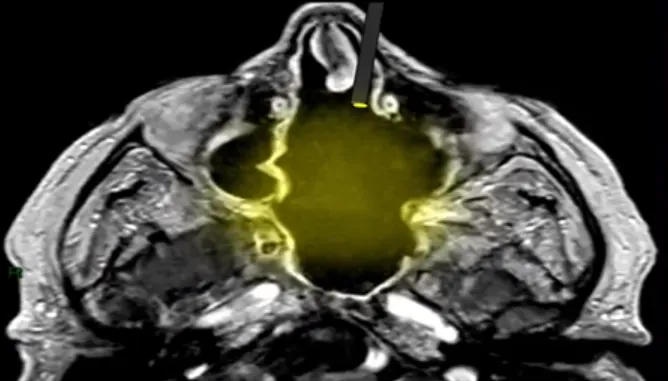

上面那个动图是不是不够直观,那看福教授列出的两幅图对比:

微侵袭经鼻神经内镜入路,对鼻腔结构破坏更少,术后并发症更少。

而开放情况下,很明显出现了和李类似的情况,鼻腔结构没了。

福教授:“鼻腔的结构,内镜手术前是什么样子,手术后也应该维持原样!”